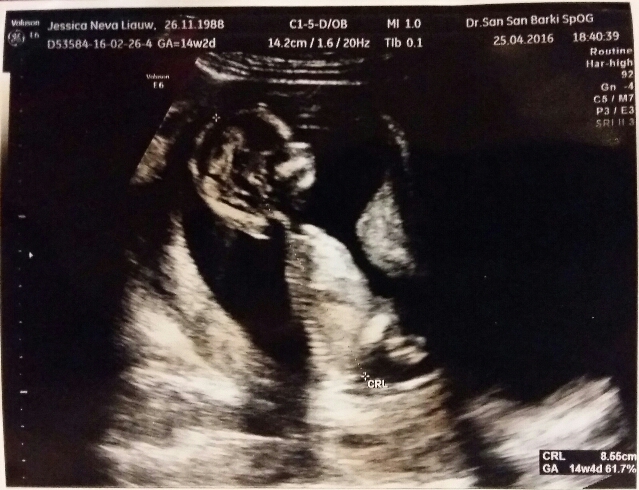

Happy news, my baby is now 14 weeks old. Length wise and heart wise, it’s healthy and growing well. Thank you Jesus! I’ve only gained 1kg so far (whatttt?!) But I’ve started to notice the growth in my bump. My pants are getting tighter but as I have lots of loose pants, I might still be able to fit into my bigger jeans until next month. Key word is “might”.

Look at that little nose and lips!!! Hellooooo baby! Kk Nathan loves you eventhough I’m sure he hasn’t comprehend you thoroughly. Nathan still loves kissing my tummy and each time it melts my heart.

Baby’s heart beat at 155bpm. Still the sweetest sound on earth. We also try to find out the gender of the baby but we couldn’t. It was crossing its feet tightly so we can’t see if there’s anything in between. Too bad (or good thing?) that we can’t start shopping now. Hahahaha.